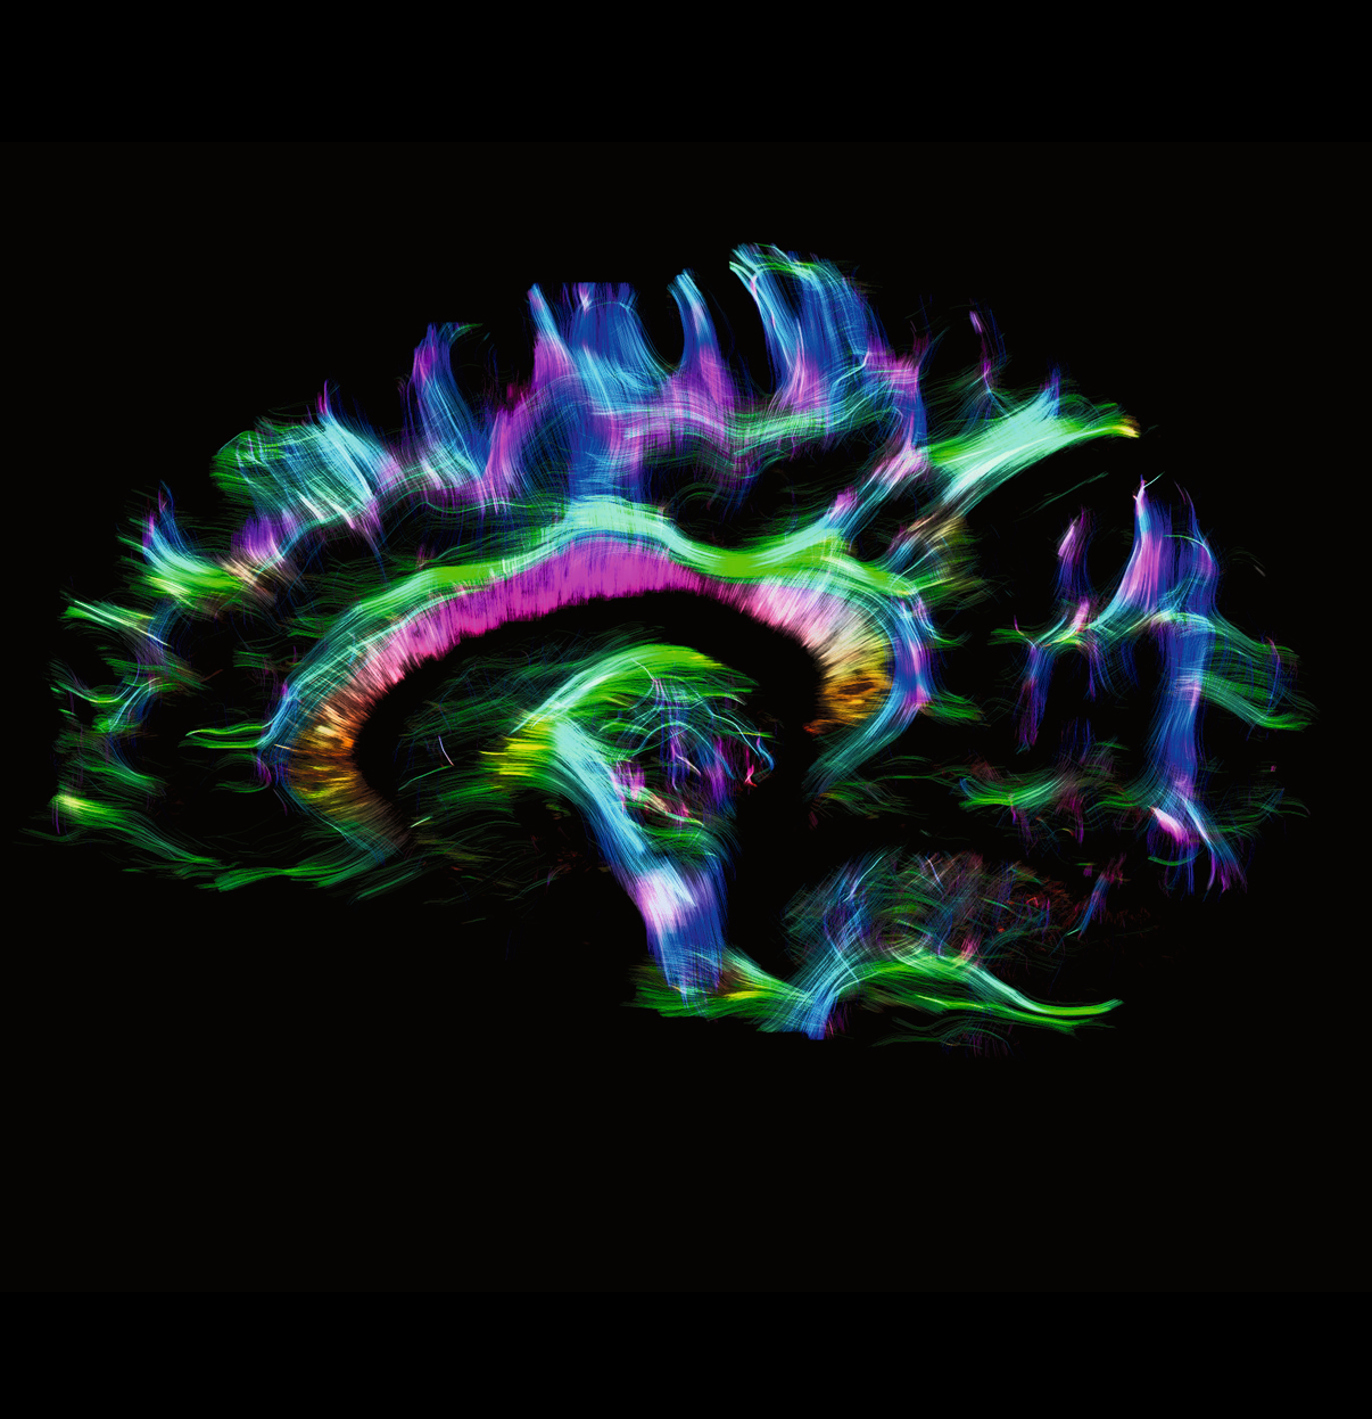

Enhanced Gradient Strength for Unprecedented Precision

With a remarkable gradient strength of 130 mT/m and a slew rate of 250 T/m/s, the MAGNETOM Terra.X takes imaging precision to unprecedented levels compared to conventional systems equipped with 80 mT/m gradients. This enhanced gradient strength facilitates faster and more detailed imaging, allowing us to push the boundaries of what is possible in research and clinical diagnostics. A huge boost for functional, diffusion and structural MRI capabilities.

Revolutionary Ultra IQ Technology and Deep Resolve

The Siemens Healthineers MAGNETOM Terra.X is equipped with Ultra IQ Technology, including dynamic pTx, unlocking the full potential of 7T MRI. This revolutionary technology, coupled with Deep Resolve, leads to previously unheard resolution and acquisition speed. Researchers at Campus Biotech can now delve deeper into the intricacies of biological structures, paving the way for groundbreaking discoveries and advancements in medical knowledge.